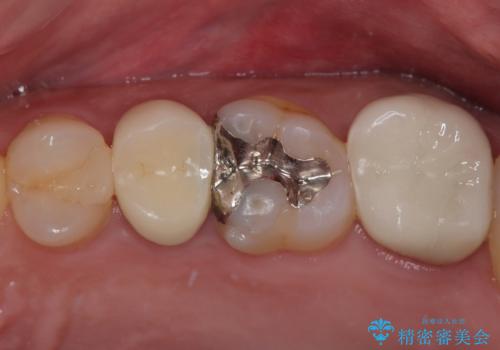

- 歯の間に物が詰まるとのことで来院された患者様です。以前に歯冠部の神経の一部を取り除き、MTAセメントという特殊なセメントを充填し、歯根部の神経を温存する生活歯髄療法(VPT)を行われておりセラミックの詰め物にて修復されていました。セラミックの詰め物が少し欠けたことにより食べ物が挟まってしまう状況でした。

まず神経の生活反応を確認し、今回はセラミックの詰め物のやり替えではなく、セラミックのかぶせ物で治療を行っていくこととしました。

拡大鏡視野下で、セラミックの詰め物、虫歯の除去を行い、オールセラミッククラウンに適した形に整えました。